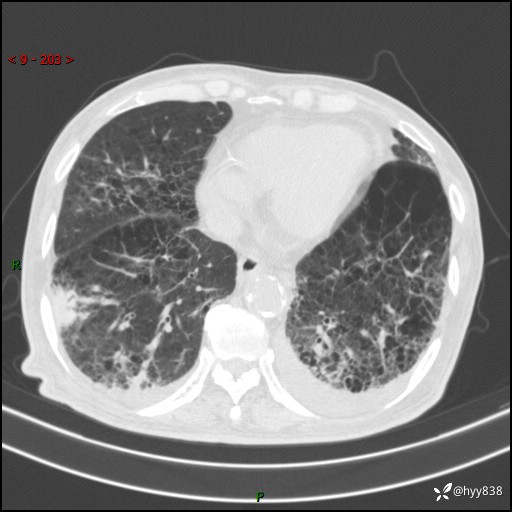

老年男性,间断咳嗽咳痰20余年,加重伴发热1天。呼吸科疑难病例讨论---结果公布

主诉:间断咳嗽咳痰20余年,加重伴发热1天

简要病史:家属代诉患者于20余年前无明显诱因出现咳嗽咳痰,痰为白色泡沫状,未行特殊治疗,不伴胸痛、胸闷、气喘、咳血等不适,1天前上午患者无明显出现发热,查体温39℃,伴咳嗽,咳痰无力,自行予以物理降温对症治疗,今晨2点左右再次出现发热,体温达40℃,自行服用复方氨酚烷胺对症治疗,凌晨3点左右复测体温38.2℃,现患者为求进一步诊治于今日就诊于我院门诊,行胸部CT提示双肺感染,遂以“肺部感染”收入我科。 患者本次起病来精神、食欲、睡眠欠佳,体力下降,体重无明显变化。

辅助检查:CT

临床诊断:感染

讨论:病变性质?

胸部CT平扫